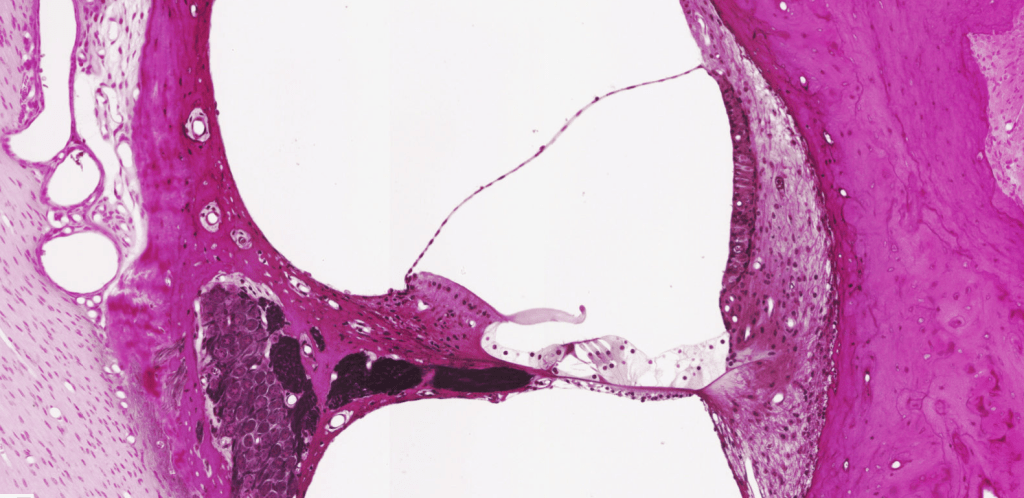

CONDUCTO COCLEAR

Identifique las rampas y las membranas a lo largo del conducto coclear.

Órgano de Corti, HyE.

Conducto coclear posiblemente teñido con Tetraóxido de Osmio.

Identifique las membranas a lo largo del conducto coclear.

Identifique las rampas a lo largo del conducto coclear.